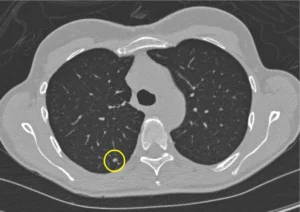

CT (computed tomography) imaging plays a pivotal role in the detection, characterization, and staging of various cancers throughout the body. The ability of CT scans

CT (computed tomography) imaging plays a pivotal role in the detection, characterization, and staging of various cancers throughout the body. The ability of CT scans